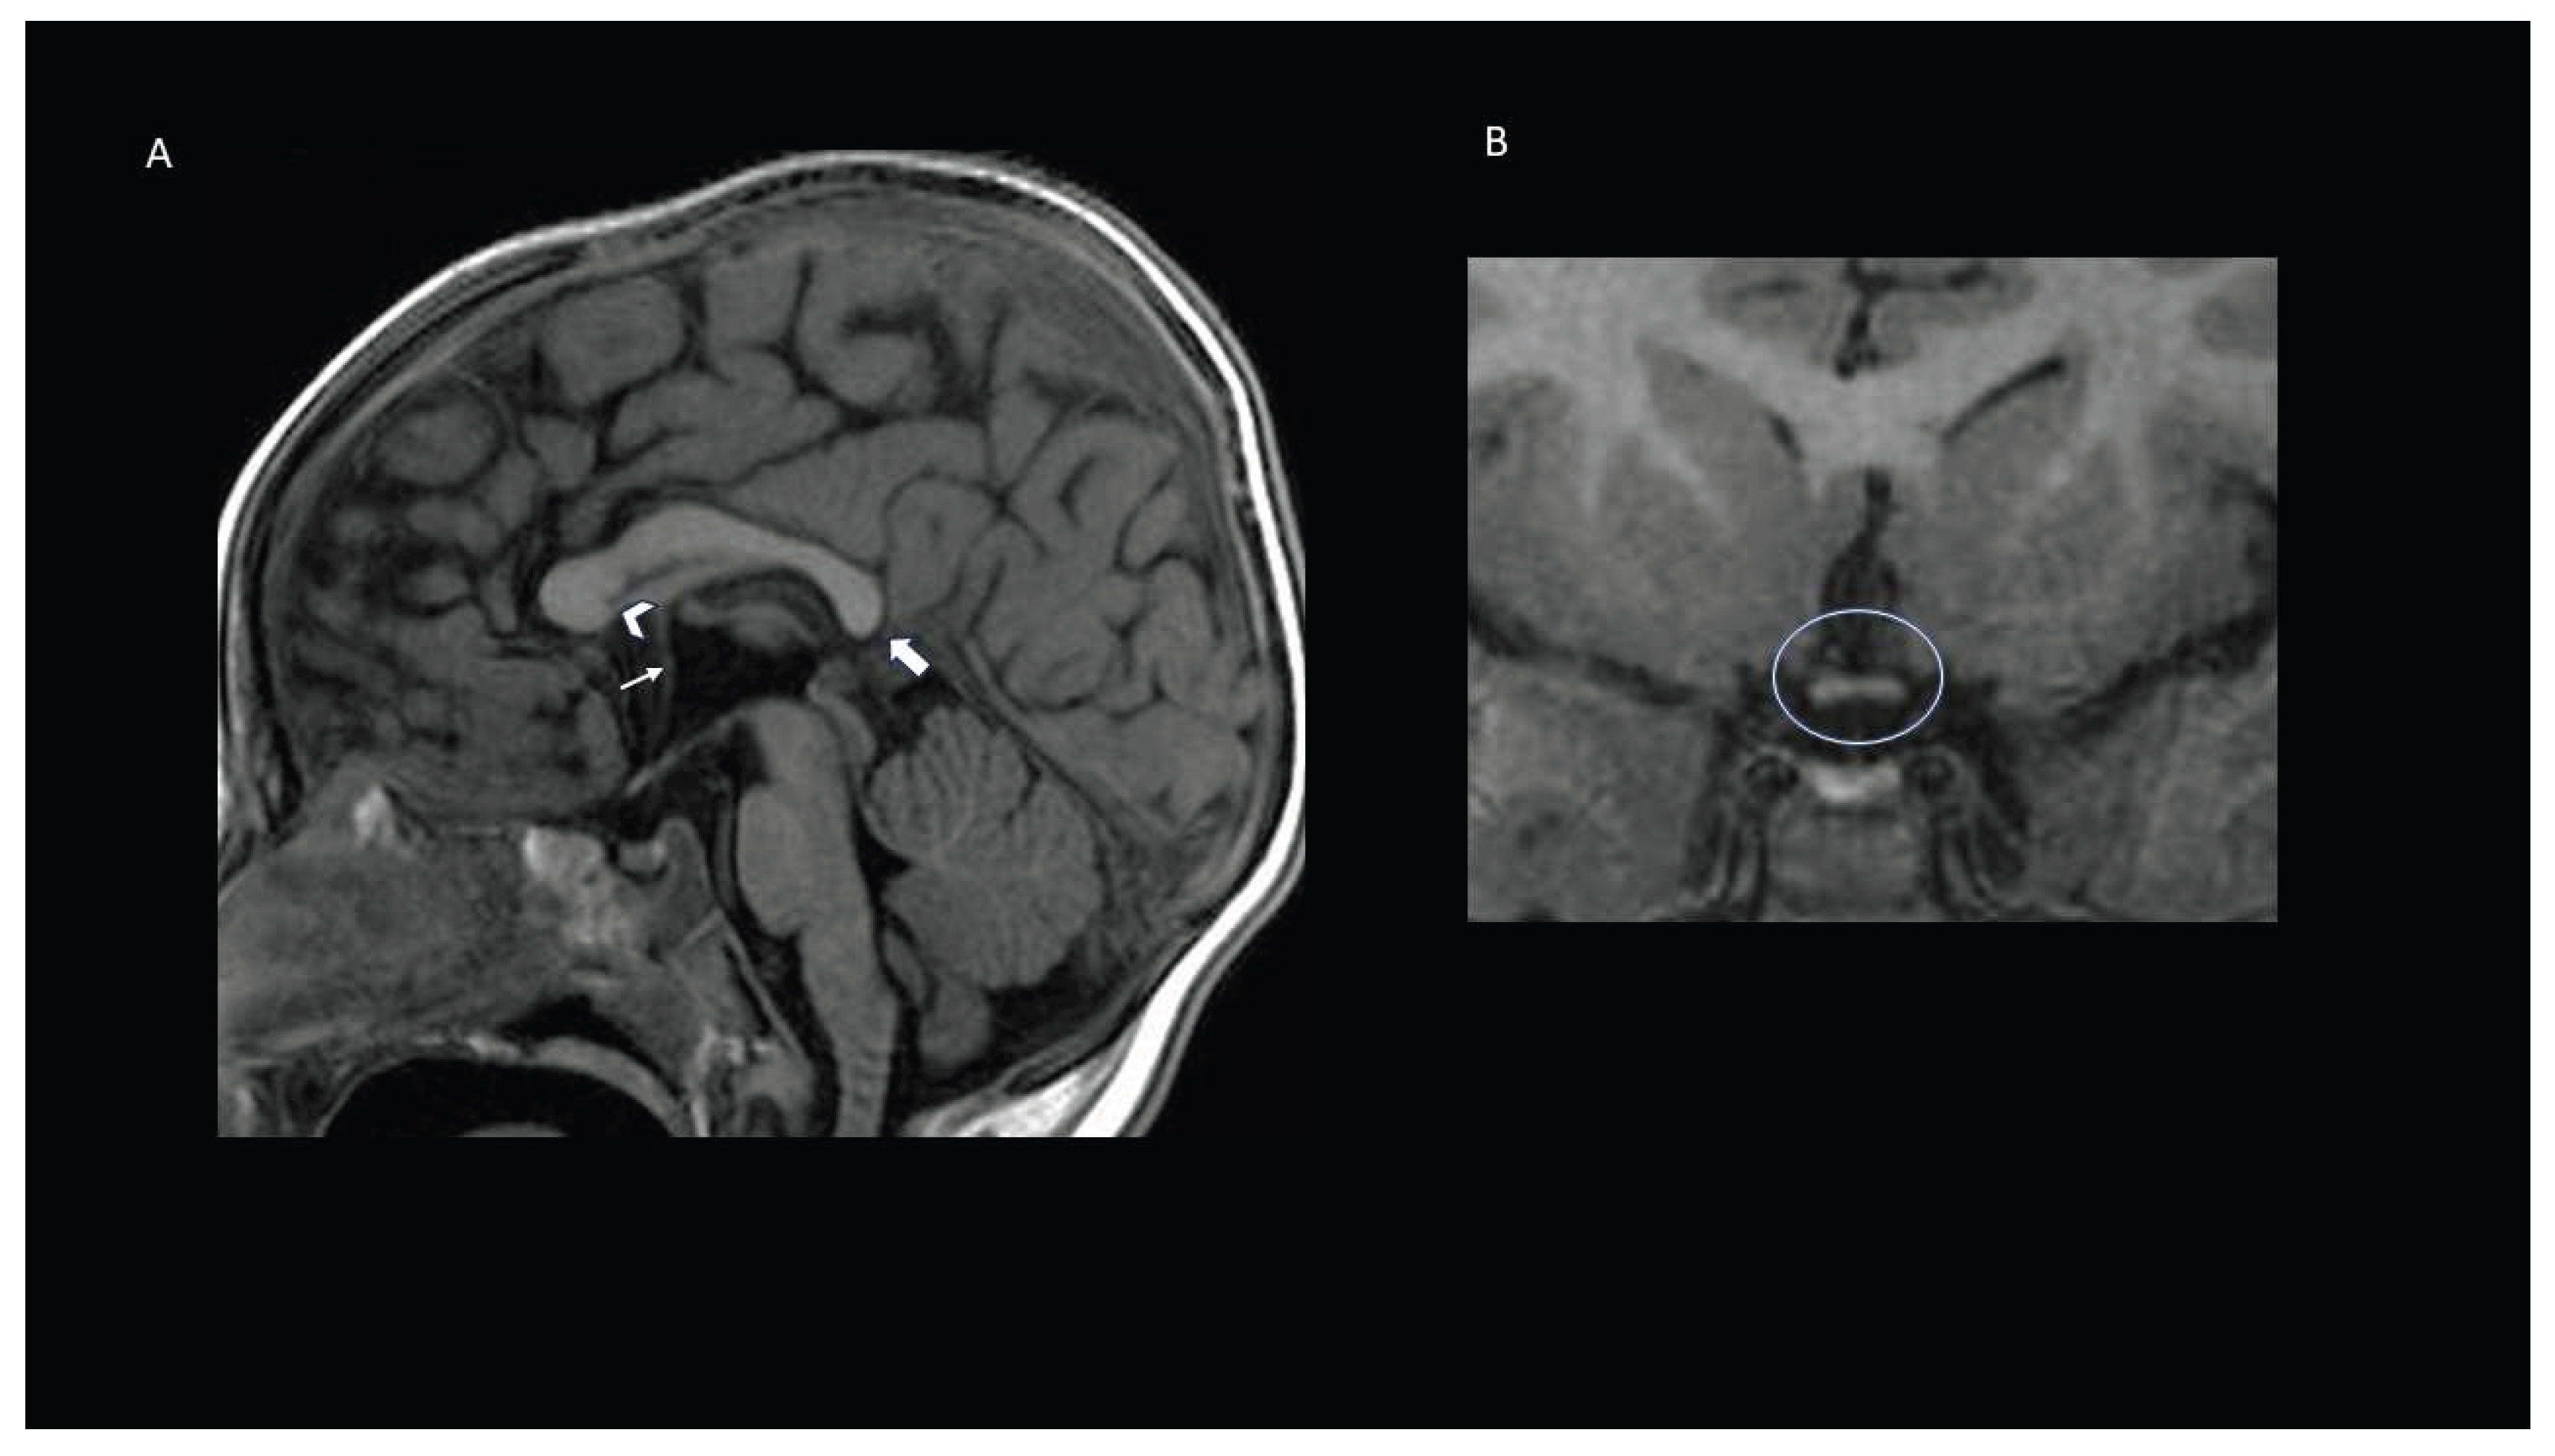

| p.(Val317Ile) | Missense GoF | M | 6 | Generalized/myoclonic mainly during febrile episodes or intercurrent illnesses | Hypotonia, walking at the age of 20 months, swallowing difficulties for liquids | Moderate-to-severe | Delayed, first word wat the age of 2; At the age of 6 years two-words associations | No | No | White matter hyperintensities, temporal horns dysmorphism with hippocampal eversion, dysmorphic corpus callosum and thin optic chiasma. | This study |